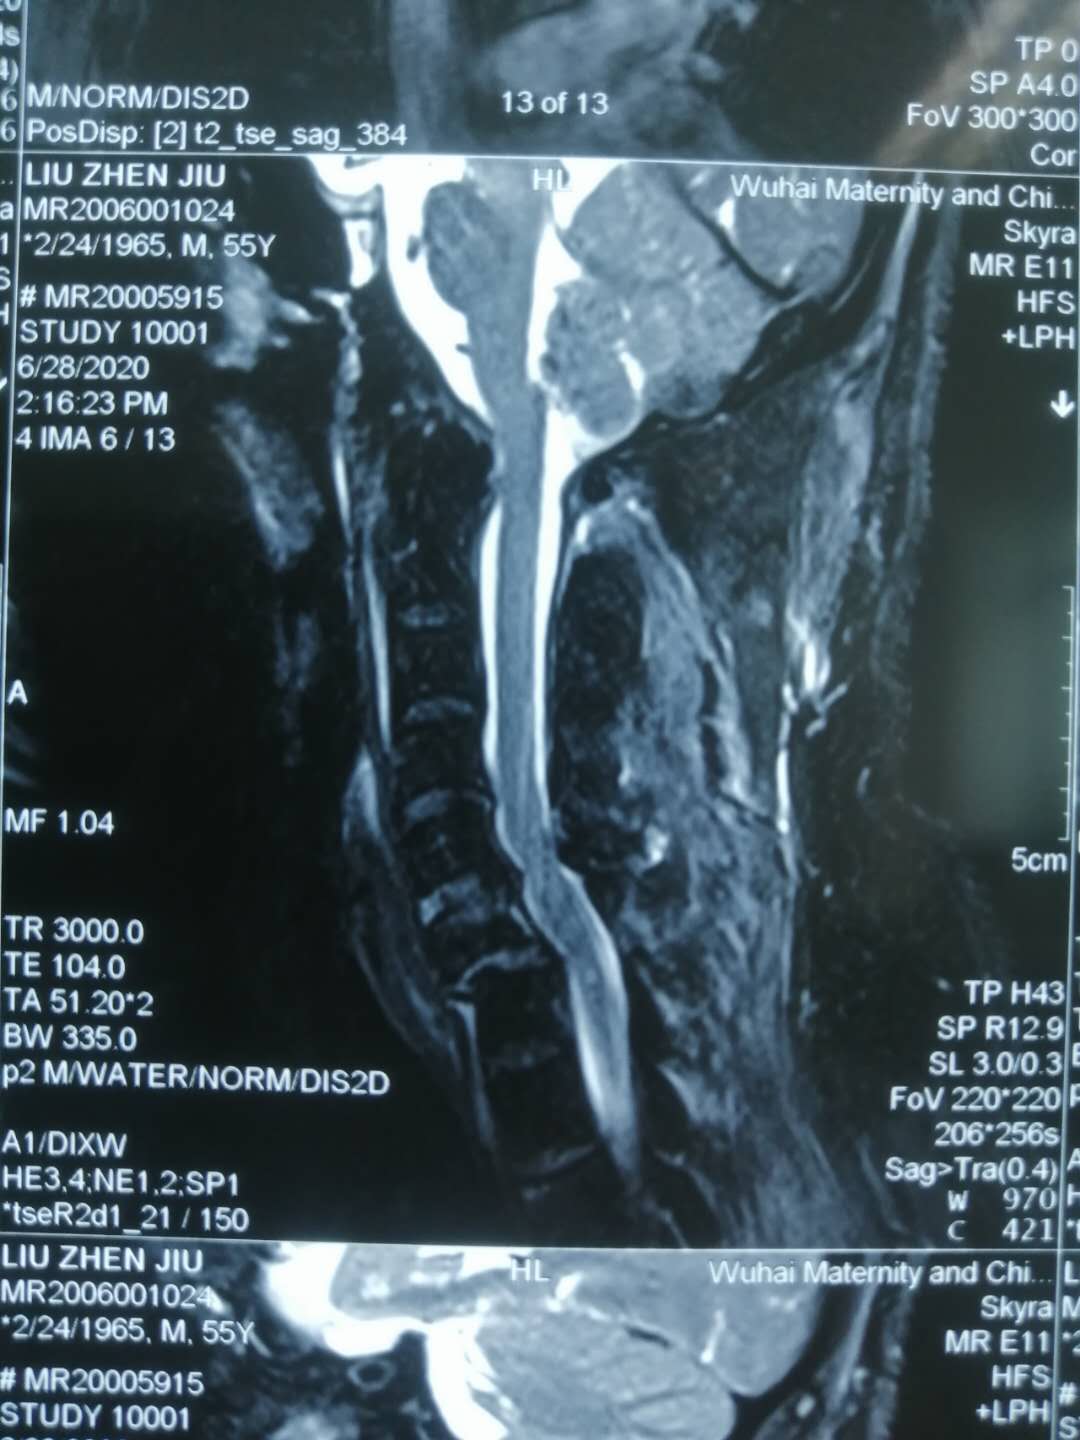

经CT显示,刘师傅胸部左侧肋骨多处骨折、肺部挫裂伤、颈部六七颈椎骨折脱位伴不完全瘫痪,“钢铁脊梁”组组长主任医师刘涛立即立即联系手术室备台,同时打电话叫来脊柱团队组员副主任医师张运动、住院医师张治河、住院医师王继龙,当天连夜为刘师傅进行“颈椎前路骨折脱位切开复位颈椎间盘切除椎间植骨融合CAGE植入椎管减压钛板前路固定术”。

手术从晚上11点一直持续凌晨3点,术后,刘师傅双上下肢刺痛症状减轻,肌力有所恢复,一周后,刘师傅双上下肢刺痛感基本消失,肌力恢复7成左右。由于刘师傅当时身体多处受伤,多部位同时手术明显不现实,不但术中术后患者体位无法摆放,多部位开放创口对机体也是相当大的损害。“家有三件事,先从紧处来”,等 刘师傅颈椎受限解除后,胸心外科主任王洪波、骨科主任医师刘涛联合为刘师傅进行胸部手术。两周后,刘师傅总体恢复情况良好,双上下肢肌力已基本恢复,带着支具便可下地走路。